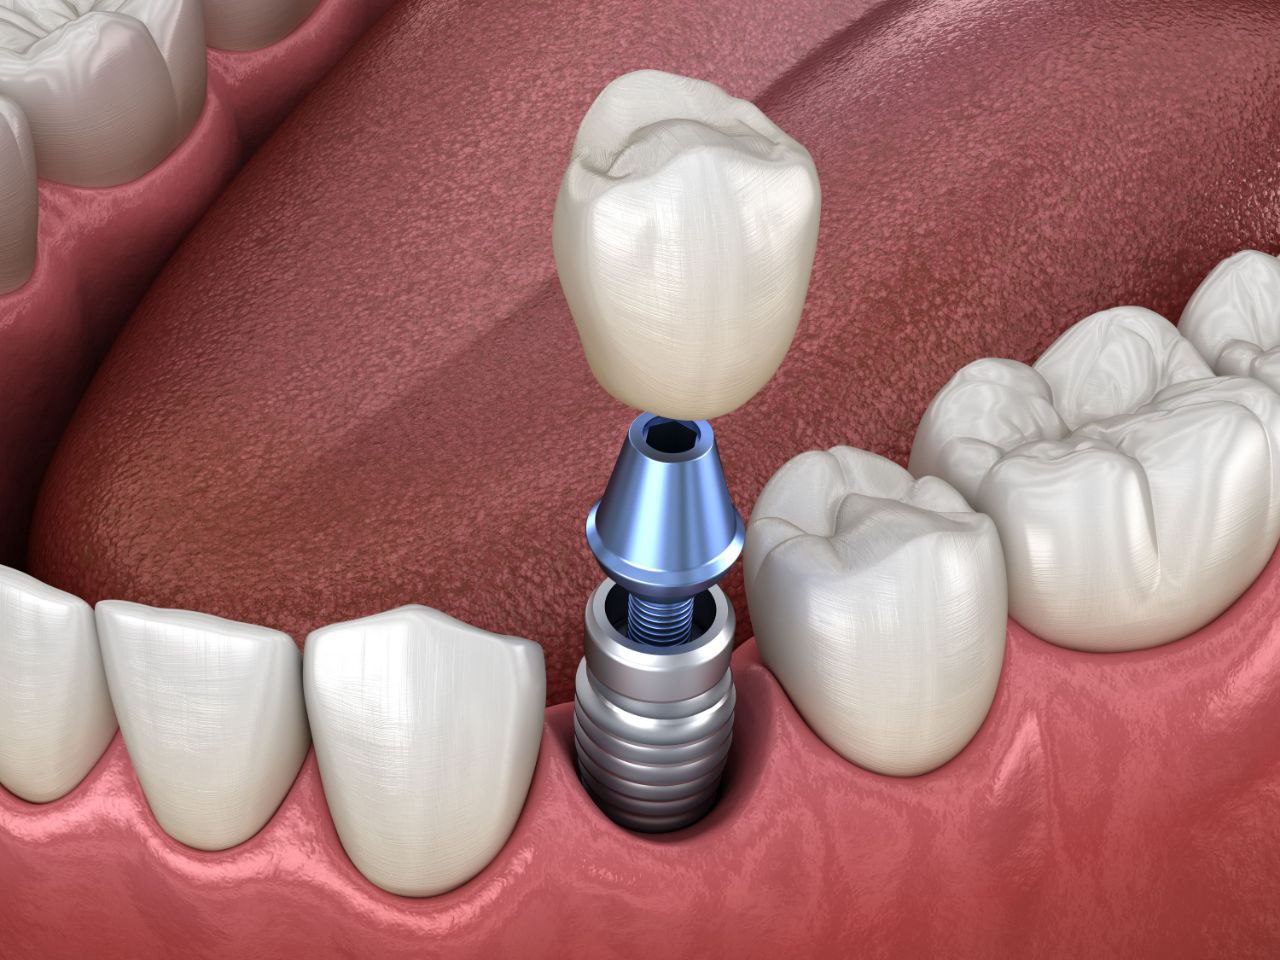

Коронки на имплантат

Протезирование на имплантах — полное восстановление красоты и функциональности зуба.

Это самый современный и очень естественный способ восстановления утраченных зубов, предотвращают атрофию костной ткани челюсти. Эстетический результат при этот выше чем , при другом способе протезирования зубов.

Протезирование на имплантах заключается в том, что коронки или протезы фиксируются на вживленные в челюсти титановые импланты. При этом сроки протезирования зависят от того какая методика имплантации проводилась.

На имплантаты можно делать любые виды коронок — от пластмассовых (в качестве временных) до циркониевых, которые обладают лучшими эстетическими, прочностными и биологическими свойствами.